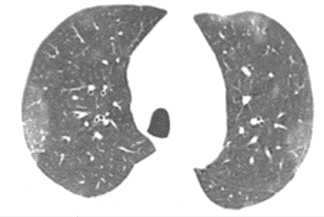

Descrição das figuras 1, 2 e 3: Tomografia computadorizada de tórax no momento da admissão. Esparsas opacidades em vidro fosco bilaterais, com envolvimento de mais de um lobo pulmonar e com distribuição predominantemente periférica. Em associação às áreas em vidro fosco, pode ocorrer ainda espessamento dos septos interlobulares, caracterizando o padrão de pavimentação em mosaico.

• Opacidades em vidro fosco, bilaterais, acometendo a maioria dos lobos pulmonares (acometimento multilobar), assimétricas e com predomínio na periferia dos pulmões;

• Em associação às áreas em vidro fosco, pode coexistir o espessamento dos septos interlobulares, caracterizando o padrão de pavimentação em mosaico;